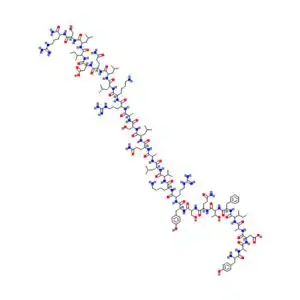

The Hexarelin CJC-1295 stack is a combination of two peptides: Hexarelin and CJC-1295. Hexarelin is a powerful growth hormone-releasing peptide (GHRP) that stimulates the pituitary gland to produce more growth hormone.

CJC-1295, a synthetic peptide, promotes the release of growth hormone by targeting the hypothalamus and pituitary. Together, they work synergistically to boost growth hormone levels, thereby promoting tissue regeneration and healing.

Growth hormone plays a crucial role in collagen production, which is a key component of joint and tendon health. This peptide stack has the potential to expedite recovery from injuries or surgeries, particularly in research contexts.

By stimulating the pituitary gland to release more growth hormone, the Hexarelin CJC-1295 stack promotes the production of collagen and enhances the repair of damaged tissues.

This peptide combination is also thought to increase the availability of insulin-like growth factor 1 (IGF-1), which aids in the proliferation and differentiation of cells that form connective tissues.

Hexarelin and CJC-1295 work together to elevate growth hormone levels, facilitating the repair of tissues that have been damaged due to injury or degeneration.

Hexarelin is a well-known peptide for stimulating the release of growth hormone, and it has shown effectiveness in promoting the regeneration of damaged tissues, including tendons and cartilage.

Hexarelin, being a potent GH-releasing peptide, ensures that the growth hormone release is maximized, leading to faster collagen synthesis and enhanced repair of damaged connective tissues. This combination can be extremely beneficial for research aimed at accelerating recovery in individuals with musculoskeletal injuries.

Hexarelin stimulates rapid growth hormone release, while CJC-1295 extends growth hormone and IGF-1 exposure. Combined, they produce a stronger, longer-lasting anabolic signal than Hexarelin alone. This synergy may enhance tissue repair and recovery processes, though head-to-head clinical comparisons and outcome-based trials are still lacking.